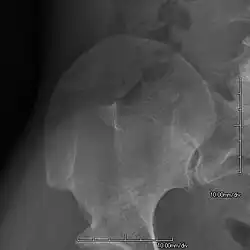

- The elbows may have limited motion (e.g., limited pronation, supination, extension).

- Subluxation of the radial head may occur.

- Arthrodysplasia of the elbows is reported in approximately 75% of patients.

An elbow of a man with nail–patella syndrome (NPS)

-

This is a view from a different angle of the same man's other elbow